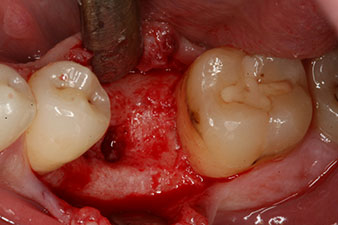

Este habría permitido una cicatrización abierta o incluso un tratamiento inmediato. Sin embargo, como no se disponía de suficiente hueso en la parte crestal del implante, el área se aumentó con las virutas óseas recopiladas durante la preparación del lecho del implante y se suturó para que no penetrara saliva.

Dos meses después, el implante se expuso y se introdujo un pilar de cicatrización (no hay figura).

Después de la cicatrización de los tejidos blandos, se volvió a determinar la estabilidad del implante antes de continuar con el tratamiento protésico.

Los dos valores eran prácticamente idénticos y se encontraban en la transición del área media a la alta; en este punto cabe reseñar que el valor más bajo sirve siempre como referencia para establecer el tratamiento adecuado.

Con ello, fue posible documentar una correcta osteointegración y una estabilidad biológica suficiente, lo que permitió realizar una conformación en la misma sesión.